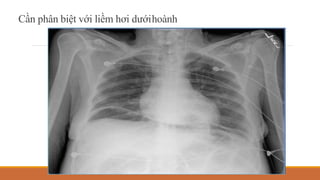

DẤU HIỆU VÒM HOÀNH LIÊN TỤC

Levin mô tả năm 1973

Bình thường không thấy phần giữa của cơ hoành do áp vào tim

Khí nằm giữa tim và cơ hoành tạo ra giao diện mô-khí

Thấy trên XQ thế thẳng đứng

Điển hình của tràn khí trung thất, có thể gặp trong: tràn khí ổ bụng, tràn khí

màng tim

Cần phân biệt với liềm hơi dướihoành